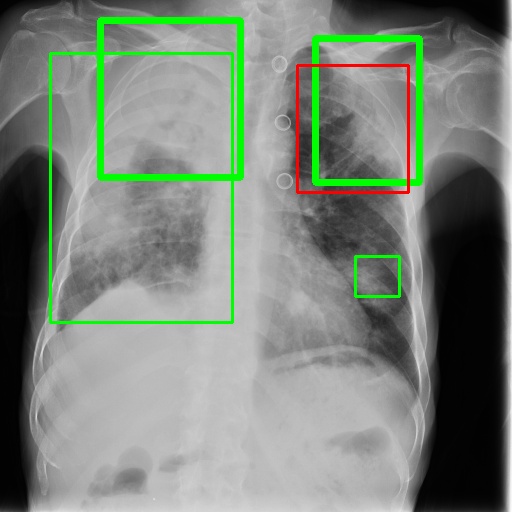

To achieve our goal, our TBX11K dataset includes bounding box annotations for TB infection areas in CXR images. To the best of our knowledge, this is the first dataset designed for TB infection area detection. These annotations are carried out by experienced radiologists from top hospitals. Specifically, each TB CXR image in the dataset is first labeled by a radiologist with 5-10 years of experience in TB diagnosis. Subsequently, another radiologist with over 10 years of experience in TB diagnosis reviews the box annotations. The radiologists do not just label bounding boxes for TB areas but also identify the type of TB (active or latent) for each box. To ensure consistency, the labeled TB types are double-checked against the image-level labels produced by the golden standard. In the event of a mismatch, the CXR image is placed in the unlabeled data for re-annotation, and the annotators do not know which CXR image was previously labeled incorrectly. If a CXR image is labeled incorrectly twice, we inform the annotators of the gold standard for that CXR image and request that they discuss how to re-annotate it. This double-checked process ensures that the annotated bounding boxes are highly reliable for TB infection area detection. Additionally, non-TB CXR images are only labeled with image-level labels produced by the golden standard. Examples of the TBX11K dataset are shown in Fig. 6, and the distribution of TB bounding box sizes is displayed in Fig. 3, indicating that most TB bounding boxes are in the range of .

6.4 Visualization

To gain insights into the learning process of deep neural networks on CXR images, we visualize the feature map of SymFormer w/ RetinaNet at a scale of . To achieve this, we employ principal component analysis (PCA) to reduce the channels of the feature map to a single channel. The resulting single-channel map is then converted into a heat map for visualization purposes. The visualization of the learned features, along with the corresponding detection results, are presented in Fig. 6. Upon analysis, we observe that the visualization of healthy cases exhibits irregular feature patterns, indicating the absence of significant abnormalities. In contrast, the visualization of sick but non-TB cases displayed some discernible highlights, potentially representing the presence of lesions. For TB cases, the highlights in the visualization map align well with the annotated TB infection areas, thereby indicating the effectiveness of the proposed SymFormer in learning deep features for TB area detection. Furthermore, in Fig. 7, we offer qualitative comparisons between the proposed SymFormer and the baseline models for TB infection area detection. As evident, SymFormer consistently delivers superior qualitative detection results.